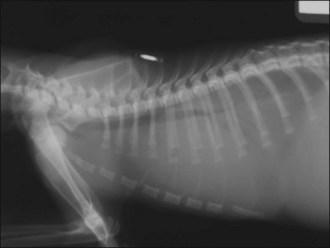

Oxygen supplementation was continued and the cat monitored closely, and she slowly began to show improvement. At the appropriate time, thoracic radiographs were taken under mild sedation (butorphanol 0.2 mg/kg i.v.) and revealed a severe diffuse bronchointerstitial lung pattern (Figure 32.5). A diagnosis of chronic bronchial disease with acute exacerbation was made.

image image

Figure 32.5 (a) Right lateral and (b) dorsoventral thoracic radiographs of a cat showing a severe diffuse bronchointerstitial lung pattern.